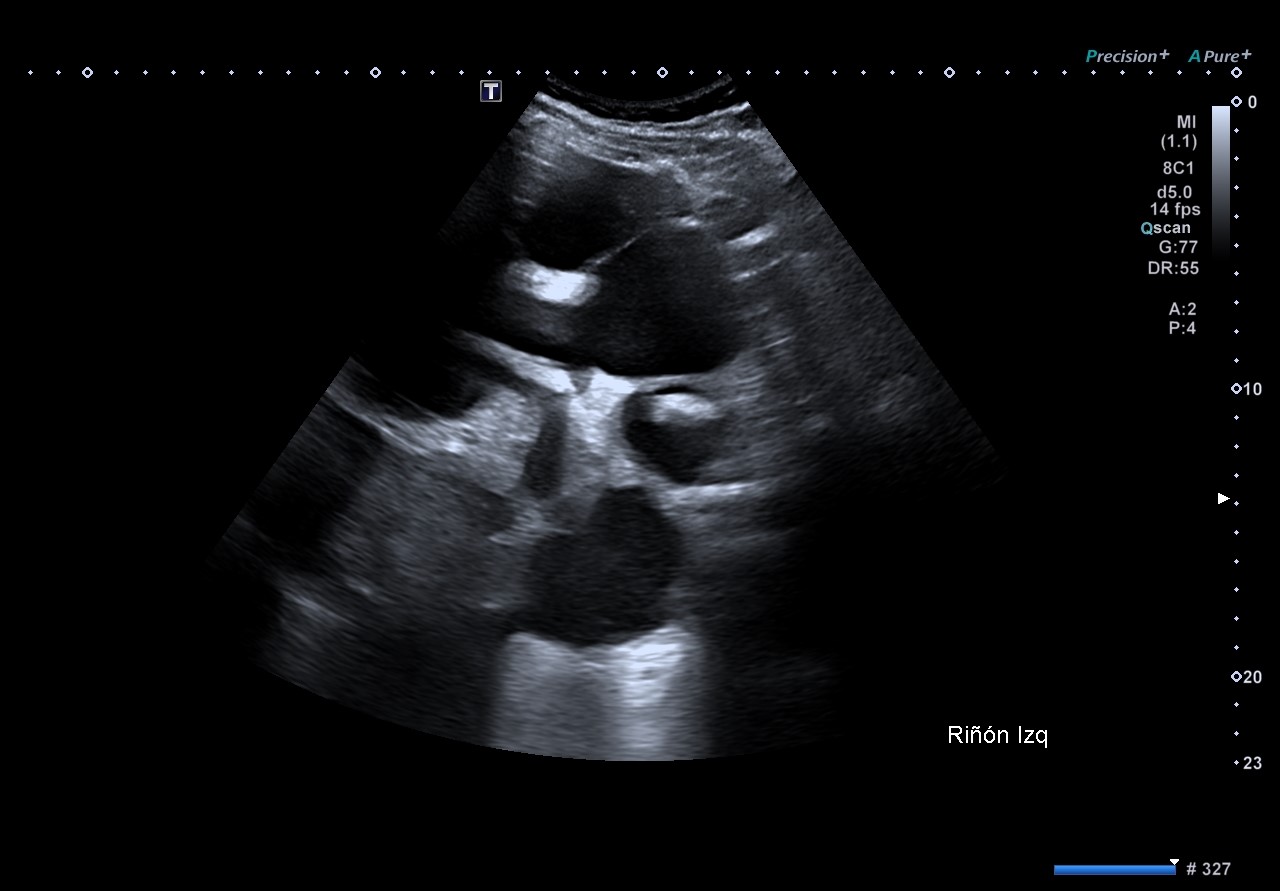

Se evidencia riñón izquierdo con hidronefrosis grado 4+, completamente desestructurado que impiden reconocer arquitectura renal normal, con múltiples imágenes anecoicas, aumentado de tamaño llegando a sobrepasar línea media. Destaca una imagen hiperecogénica con múltiples sombras acústicas posteriores, compatible con litiasis coraliforme, en concordancia con la radiografía.